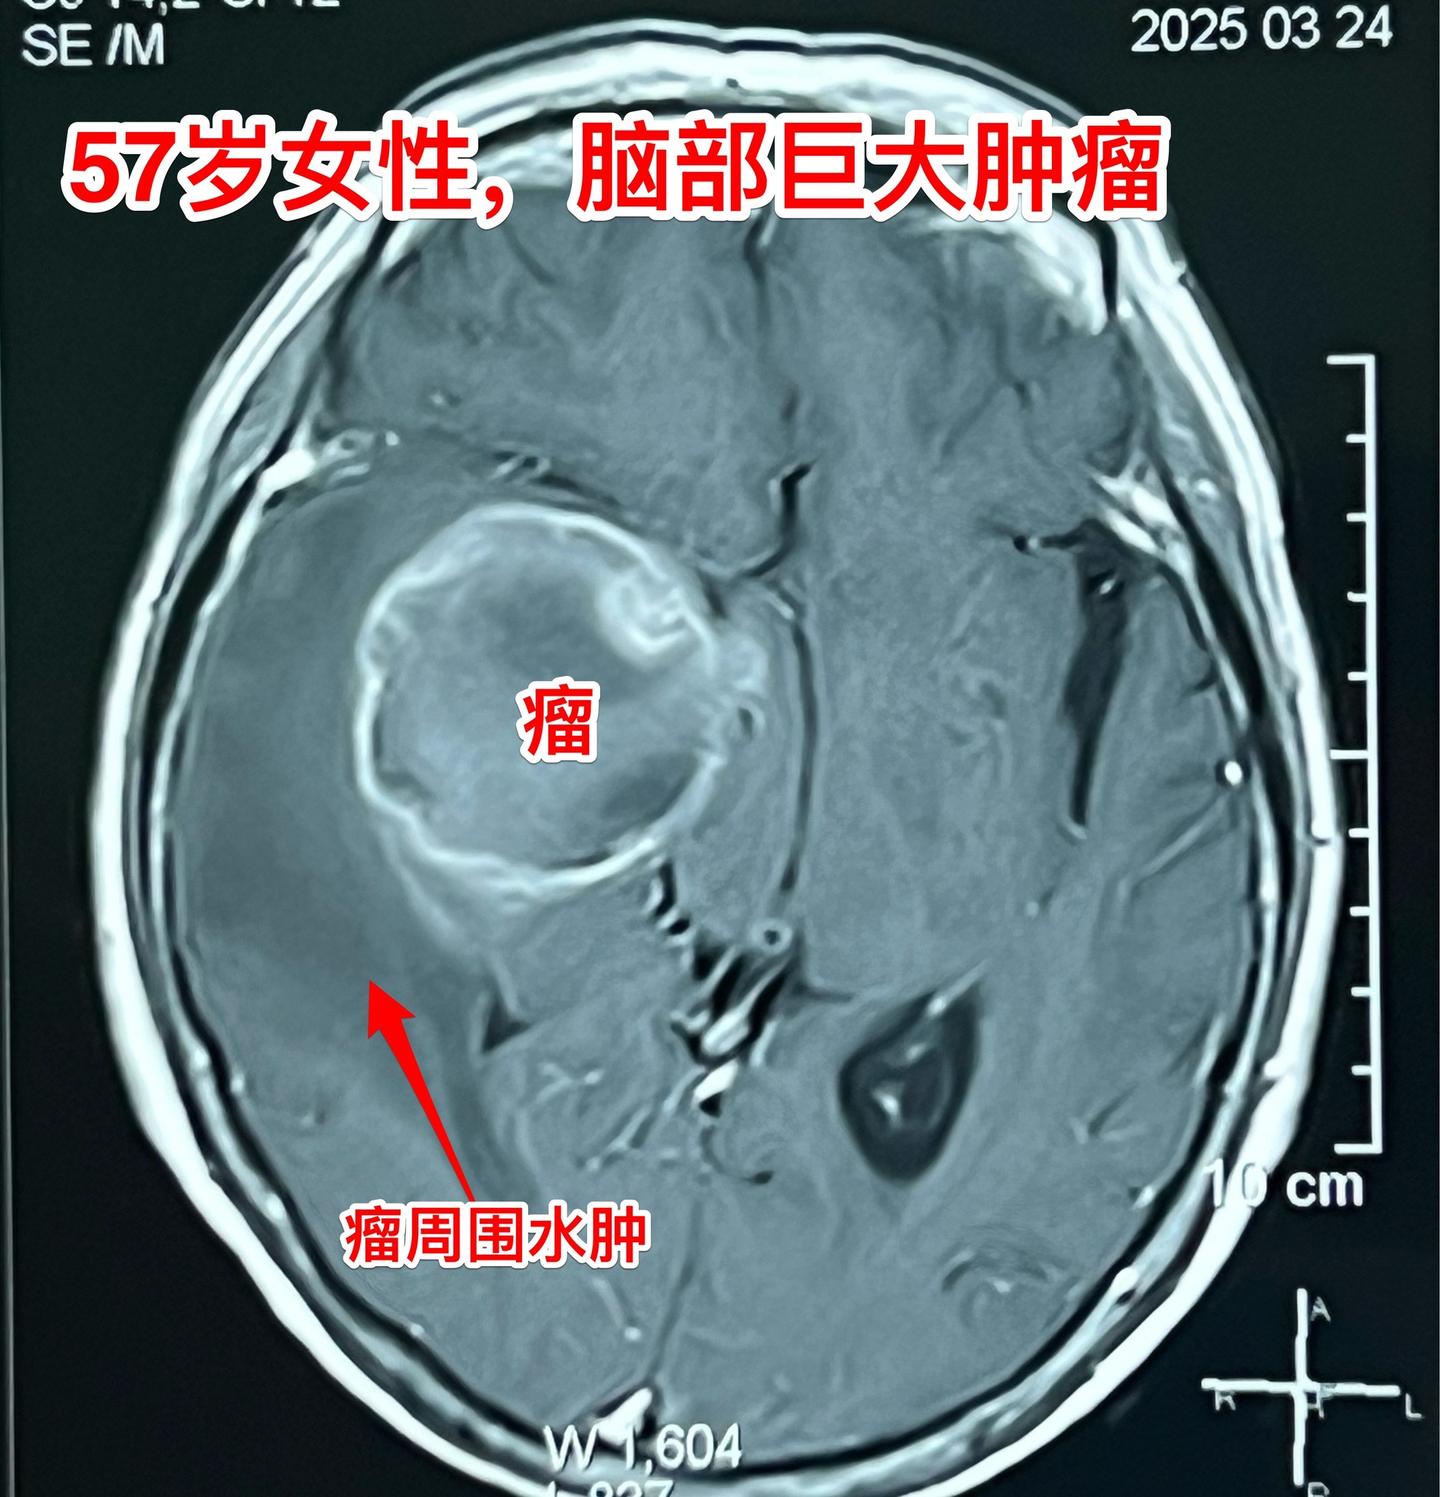

肺癌患者多年后出现脑部转移。57岁的韶关女病人在18年前患肺癌,作了手术切除肺癌并作了化疗,随后多次复查,没有发现肿瘤复发。她也在正常上班。 就在这个春节前她的婆婆去世了,她的情绪似乎受到严重影响,和平时不一样,总是担惊受怕。 三月份经家人提醒,到当地医院去作头部CT检查,结果发现脑部有个瘤,像鸡蛋那么大了!医生怀疑是胶质瘤。 3月22日到北京来找我住院。3月27日晚作了手术,手术中看见肿瘤形态符合肺癌脑转移。等待病理报告。